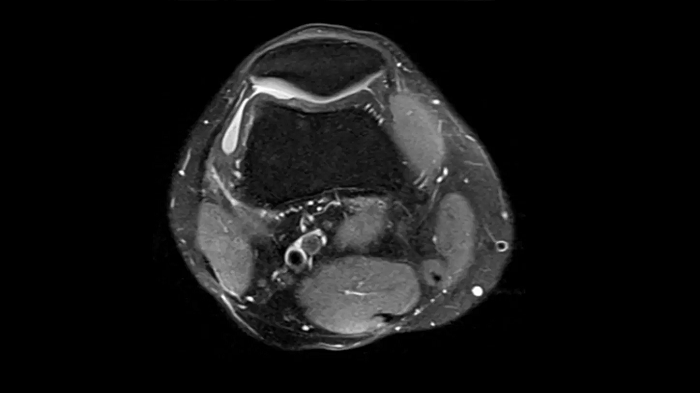

PD TSE Fat Sat with Deep Resolve and Simultaneous Multi-Slice

For clear imaging of the knee, brilliant fat suppression and performance are possible. Integrating the influence of Deep Resolve with the proven Simultaneous Multi-Slice technique.

SMS 2 | Deep Resolve Gain & Sharp

0.3 x 0.3 x 3.0 mm2

TA 2:16 minutes

MAC-ID: 7aaaa0198. Image Credit: Siemens Healthineers